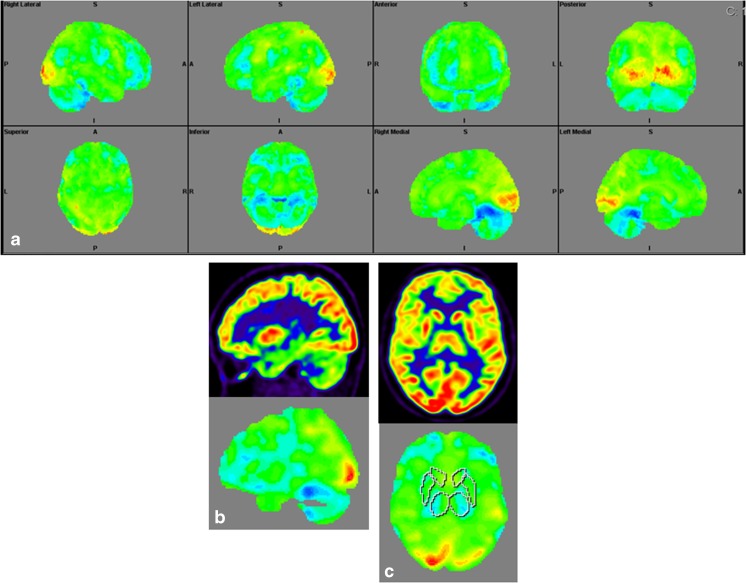

Structural Brain Imaging and [18F] FDG PET

The imaging data are summarized in Table 1 and are shown in Figs. 2, 3, 4, 5, 6, 7, and 8. Brain MRI revealed atrophy of the vermis and supratentorial white matter hyperintensities (WMH) in patients III:1 and III:2 and to a lesser degree in the index case (Figs. 2, 3, and 5). These WMH were particularly widespread in III:1 (Fig. 2). The index case was not affected by any other comorbidity usually associated with WMH, suggesting that these abnormalities may be an underlying feature of SCA19/22. WMH were not evident in the youngest patient (V:1). [18F] FDG PET revealed hypometabolism in the entire cerebellum, thalamus, prefrontal cortex (PFC), and parietal regions of the index case (IV:1) (Fig. 6). Her mother had reduced glucose metabolism not only in the PFC but also in the vermis as wells as in the motor and temporal cortex (Fig. 4). The youngest patient (V:1) had hypometabolism in the PFC, parietal, and inferior temporal regions but surprisingly not in the cerebellum (Fig. 8). In the latter structure, atrophy of the vermis was evident (Fig. 7).

Fig. 8.

Surface projections (3DSSP) of brain [18F] FDG PET findings for patient V:1. a Displays hypometabolism in the prefrontal cortex, lateral temporal cortex, and in some areas of the parietal cortex. b Metabolism in the cerebellum is normal on this midsagittal image (upper case). c FDG uptake is also normal in the basal ganglia and thalami on the coronal image (upper case); reference values in VOI templates are displayed in the lower cases of B and C